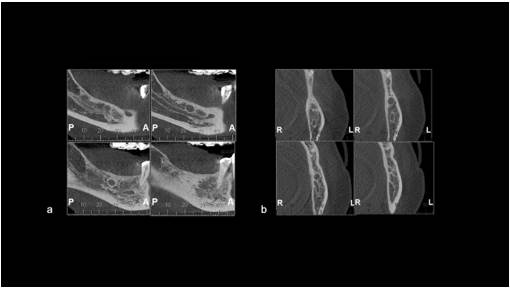

In May 2015, a 60-year-old woman presented to a private clinic for dental implant placement. However, imaging examinations revealed the presence of a lesion in the mandible. At that time, the patient reported no symptoms. Extraoral and intraoral examinations revealed no abnormal findings, such as tenderness, swelling, or pain. Her medical history was unremarkable, and no other relevant information was obtained from the anamnesis. Computed tomography revealed a hypodense lesion with a sclerotic margin measuring approximately 0.8 × 0.8 × 0.7 cm in the right posterior mandible (Figure 1a and 1b). Based on the patient’s history and clinical findings, the initial clinical diagnosis was an RC. Informed consent was obtained, and under local anesthesia, an excisional biopsy was performed. The specimen was sent to the Oral Disease Diagnostic Center (CDEO) at the Federal University of Pelotas, Brazil. The macroscopic specimen consisted of a well-defined soft tissue mass, brown in color, with a regular surface, measuring 0.5 × 0.5 × 0.2 cm. It was placed in 10% formalin and submitted for histopathological analysis.

Figure 1. Initial computed tomography (CT) scan - May 2015 - showing a unilocular hypodense lesion with a sclerotic margin measuring approximately 0.8 × 0.8 × 0.7 cm in the right posterior mandible (a: sagittal section) (b: coronal section).